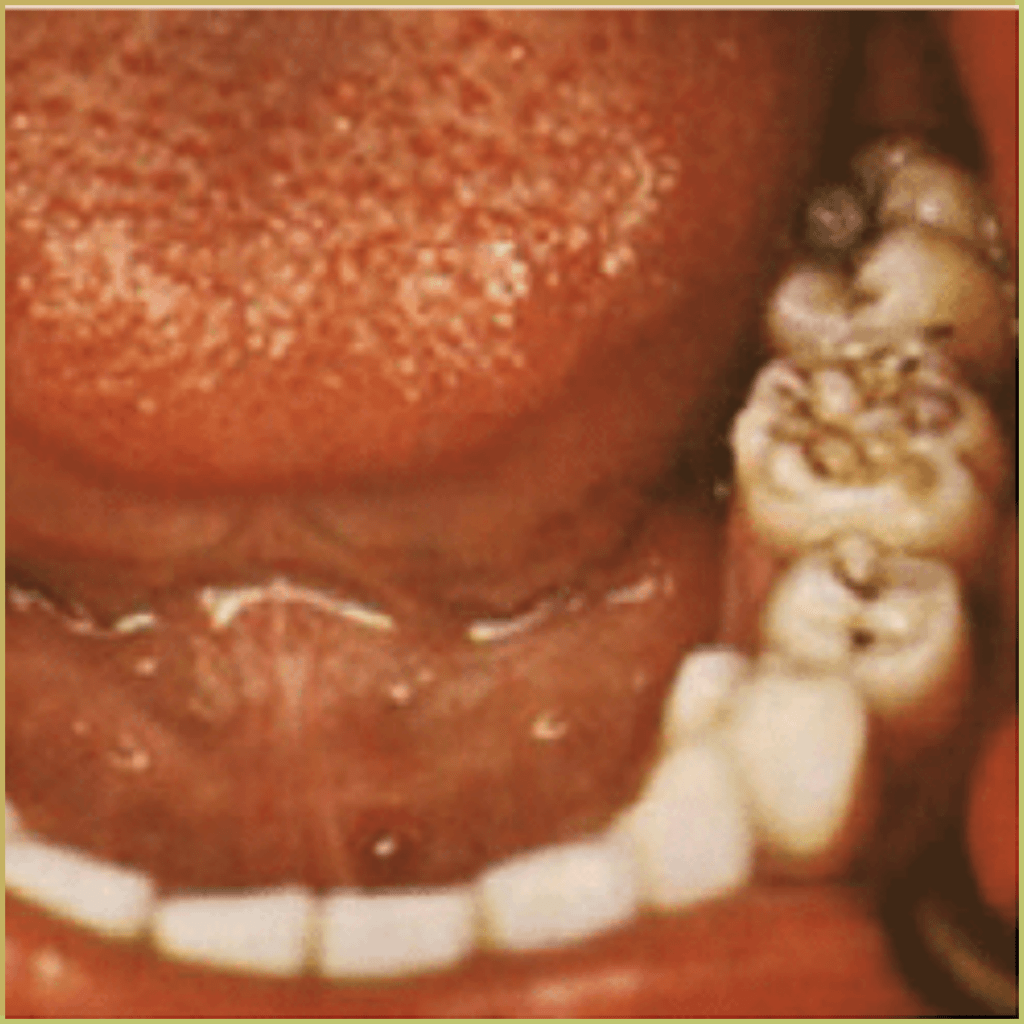

- Presents with the Hutchinson’s triad: interstitial keratitis, malformed teeth (Hutchinson incisors and mulberry molars), and eighth nerve deafness.